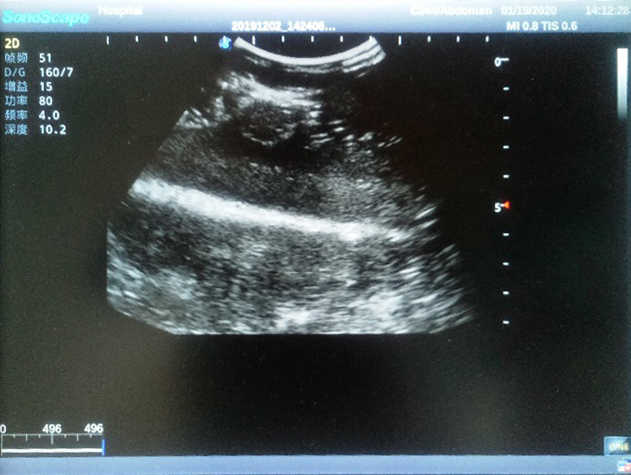

Outline

The Breast Ultrasound Examination Model allows users to develop and practice the skills necessary to gain proficiency in breast palpation, using ultrasound for normal and abnormal imaging and biopsy. It simulates adult female breasts with realistic size and appearance.

4) Biomimetic material allowing users to see clear and real normal tissues and space-occupying lesions that are hyperechoic, hypoechoic and isoechoic as they would see in the clinical environment